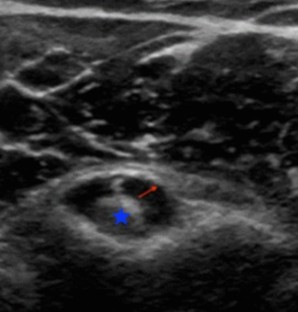

Fig. 1

Fig. 2

Fig. 3

Fig. 4

Fig. 5